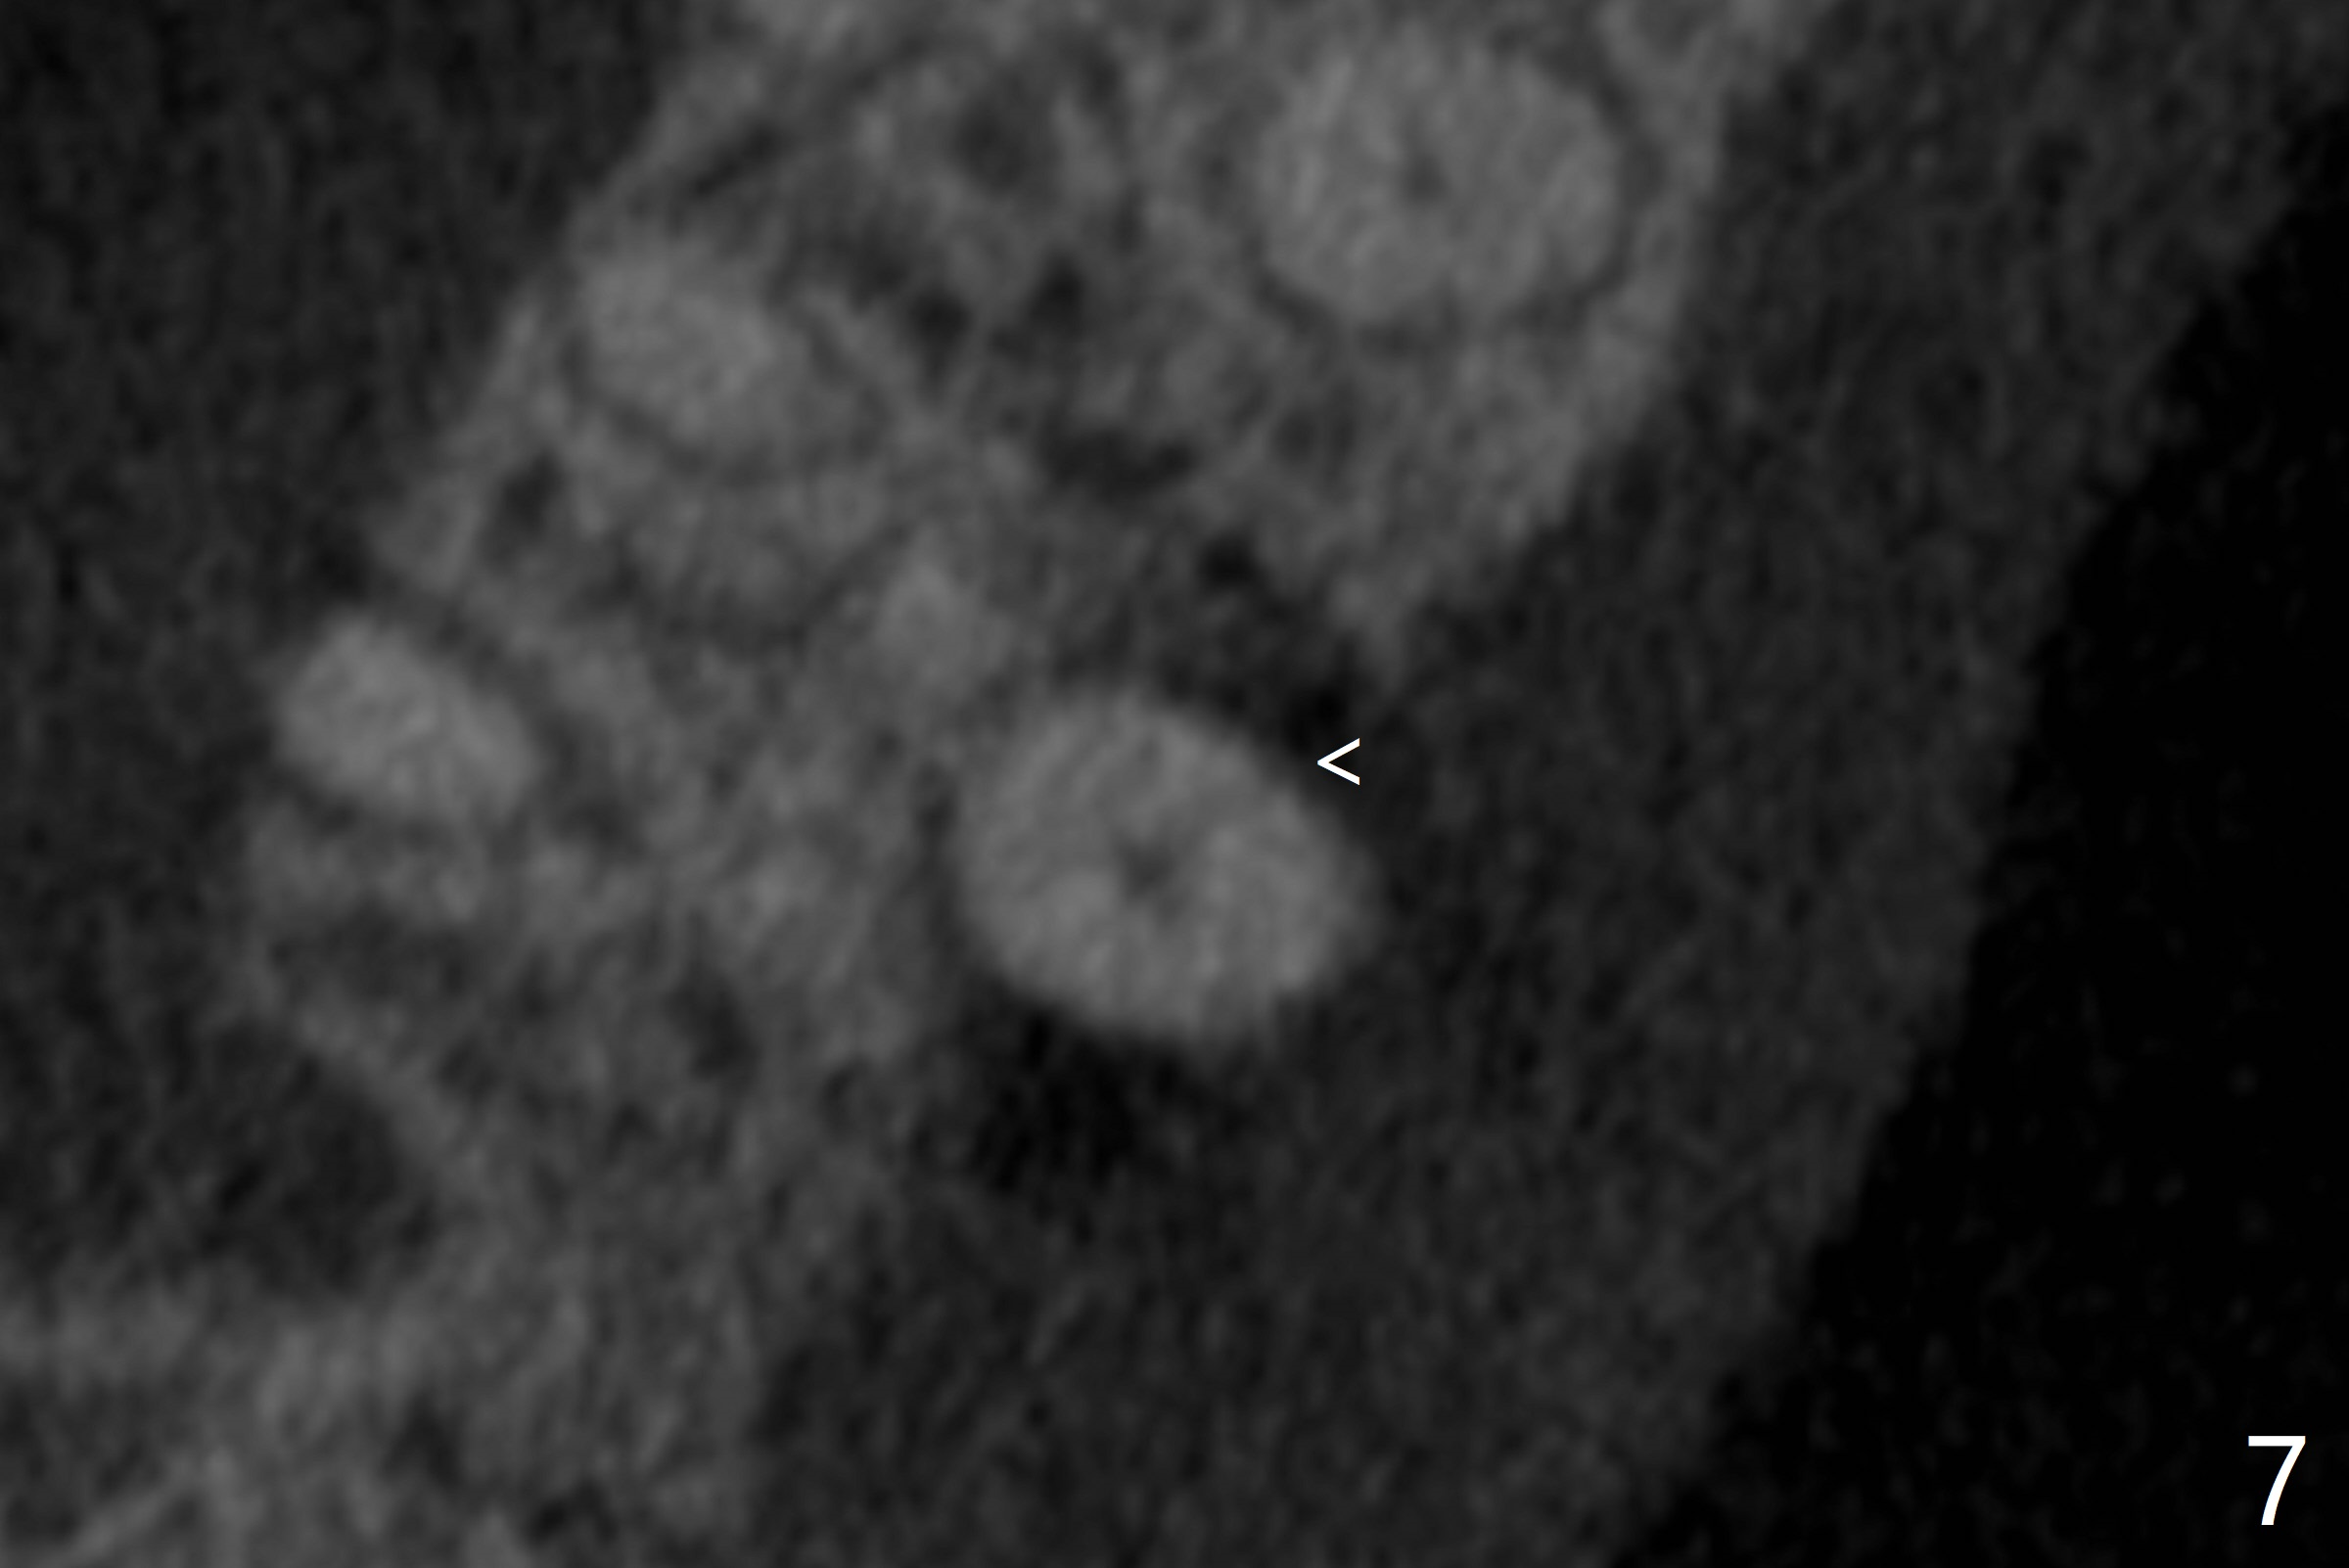

A 52-year-old man (smoker 1 ppd) has toothache in UR. The tooth #4 has severe Class V defect (Fig.1 *), periapical radio-lucency (PARL, arrow-heads) around the buccal roots and mild percu-ssion. PARL is more severe around the palatal root (Fig.2 P). Since it seems difficult to do socket preser-vation, can we do RCT to regrow bone before implant? CT coronal section shows the palatal defect of the palatal root (Fig.3,4), while sagittal one shows J defect of the palatal root, associated with root fracture (Fig.5). In fact the palatal root has transverse fracture at crestal level (Fig.6-8). The tooth #4 will be extracted for immediate implant (Fig.9,10); a 4 mm implant will be placed in the narrow space of #3 at the same time (Fig.11). The patient had symptoms consistent with aortic aneurysm. Since then smoke has been quit.